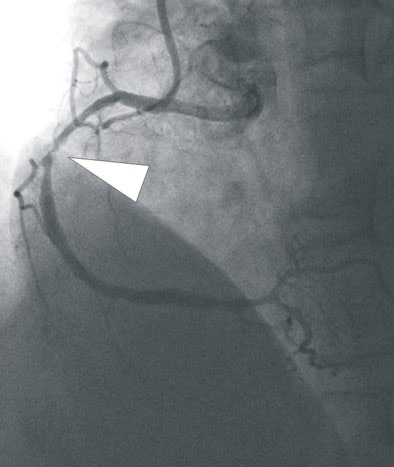

![]() |

| In a 64-year-old man with chest pain, conventional catheter angiography confirmed the coronary CTA findings, and described a 50% ostial stenosis with diffuse disease throughout the vessel and a discrete 90% stenosis in the mid right circumflex artery (RCA) (arrows). |

"Segmental comparison was performed between coronary CTA and (DSCT) myocardial segments," they wrote. "Results were also compared with findings at SPECT and/or invasive catheter angiography. Data were analyzed using the Bayesian model."